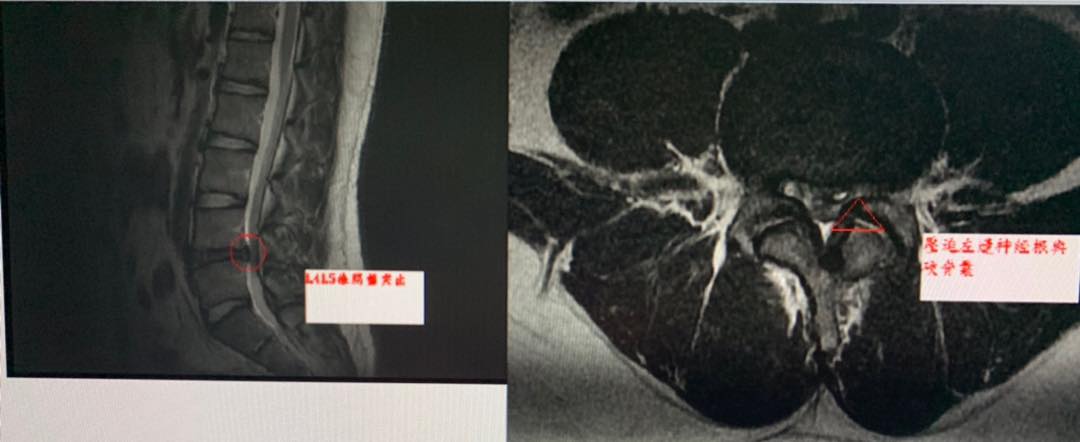

😂😂帥氣的侯同學從桃園北上來就醫,為的就是希望能夠重新恢復打網球的實力!!門診中提到他六年前曾經在某大醫院接受椎間盤微創手術,但效果仍然不如預期,一直到最近這一年腰痛又開始變嚴重,特別是早上起來腰痛如折啊,打噴嚏也會痛(代表腹壓上升椎間盤突出),再度去醫院拍片發現腰椎第四椎間盤再度突出!!(晴天霹靂啊以為動了手術就沒事啦),我很認真告訴侯同學運動姿勢不良與體重問題都可能導致椎間盤再度突出,經過教練熱情介紹接受腰椎整合針刀療法,他非常幸運的在第三次治療後就改善超過一半,於是很有信心把一個療程八次全部走完,醫師囑咐要好好保養腰椎,這只是個案而已,原本可能考慮要再次動刀的小將露出非常燦爛的微笑,並開始強化下背核心肌群跟減重作業,這樣才真正揮別腰痛夢魘,非常感謝她在療程結束後特別去側拍一段影片謝謝他在療程結束之後側拍一段影片,見證針刀醫學療法的效果,打球一整個順跟帥氣啊

「因為打網球的關係,導致椎間盤突出,疼痛長達六年。最早因為無法行走,因此去大醫院進行氣化針手術,但是腳還是會麻、腰部仍然感到疼痛。

直到最近早起時下背僵硬、打噴嚏會痛,有明顯的影響到我的生活。因此我特別從桃園北上就醫,經過3次治療後下肢無力、下背疼痛等症狀皆有明顯改善。